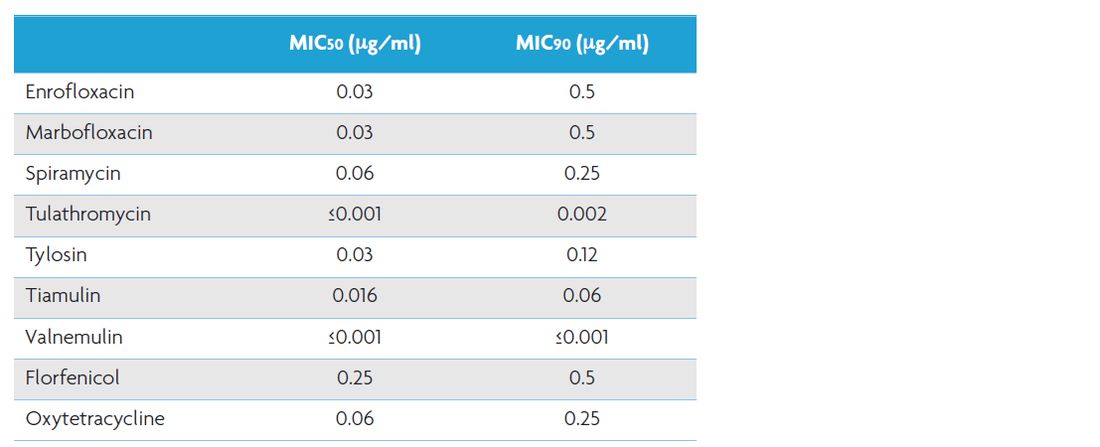

The minimal inhibitory concentration of tiamulin to inhibit growth of 90% (MIC90) of the M. hyopneumoniae strains tested is not more than 0.06μg/ml (Table 1).